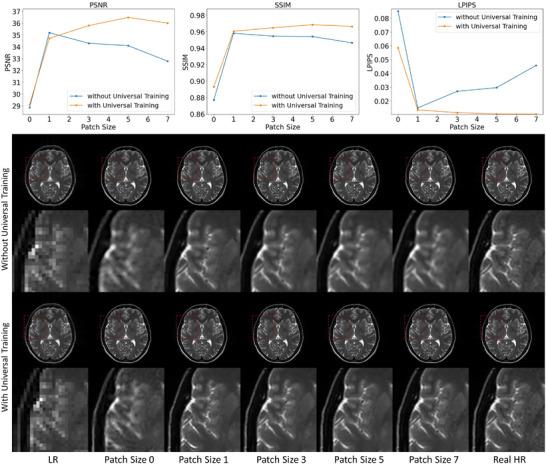

To achieve super-resolution for on-board MRI, this study proposed a universal anatomical mapping and patient-specific prior implicit neural representation (USINR) framework. Unlike traditional methods that interpolate solely based on individual on-board MR images, USINR can fully utilize the patient-specific anatomical information from a high-resolution prior MRI. In addition, USINR leverages knowledge about universal mapping between population-based prior MRIs and on-board MRIs, elevating the upper bound of super-resolution performance and enabling faster on-board fine-tuning.

USINR was evaluated on three datasets, including IXI, BraTS, and an in-house abdominal dataset. It achieved state-of-the-art performance on all of them. For example, on the BraTS dataset, USINR was trained on 1151 paired training samples (for universal anatomical mapping) and tested on 50 patients. It achieved average SSIM, PSNR, and LPIPS scores of 0.9656, 37.12, and 0.0214, respectively, significantly outperforming the published state-of-the-art method SuperFormer, whose corresponding scores were 0.9488, 35.83, and 0.0388. Furthermore, USINR can complete patient-specific training in less than one minute, rendering it a favorable solution in time-constrained ART workflows. In addition to large-scale dataset evaluations, a case study was conducted on an in-house patient at UT Southwestern Medical Center. This case study included two MRI scans (a prior scan for plan simulation and a new one for on-board imaging) from a single patient with a long interval between two scans, during which the tumor size underwent a significant change. Despite these substantial anatomical changes between prior and on-board imaging, USINR was able to accurately capture the change in tumor size, highlighting its robustness for clinical applications.

为实现机载MRI的超分辨率,本研究提出了一种通用解剖映射和患者特异性先验隐式神经表示(USINR)框架。与传统方法仅基于单个机载MR图像进行插值不同,USINR可以充分利用来自高分辨率先验MRI的患者特异性解剖信息。此外,USINR利用了基于人群的先验MRI与机载MRI之间通用映射的知识,提高了超分辨率性能的上限,并实现了更快的机载微调。

USINR在三个数据集上进行了评估,包括IXI、BraTS和一个内部腹部数据集。在所有这些数据集上,它都取得了领先的性能。例如,在BraTS数据集上,USINR在1151对训练样本(用于通用解剖映射)上进行训练,并在50名患者上进行测试。它分别实现了平均结构相似性指数(SSIM)、峰值信噪比(PSNR)和学习感知图像补丁相似度(LPIPS)分数为0.9656、37.12和0.0214,显著优于已发表的领先方法SuperFormer,其相应分数分别为0.9488、35.83和0.0388。此外,USINR可以在不到一分钟的时间内完成患者特异性训练,使其成为时间受限的ART工作流程中的理想解决方案。除了大规模数据集评估外,还在德克萨斯大学西南医学中心的一名内部患者身上进行了案例研究。该案例研究包括来自一名患者的两次MRI扫描(一次用于计划模拟的先验扫描和一次用于机载成像的新扫描),两次扫描之间间隔较长,在此期间肿瘤大小发生了显著变化。尽管先验成像和机载成像之间存在这些显著的解剖结构变化,USINR仍能够准确捕捉肿瘤大小的变化,突出了其在临床应用中的稳健性。